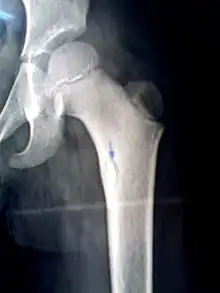

An X-ray of a child's femur showing a bony sequestrum highlighted by the blue arrow.

A sequestrum (plural: sequestra) is a piece of dead bone[1] that has become separated during the process of necrosis from normal or sound bone.